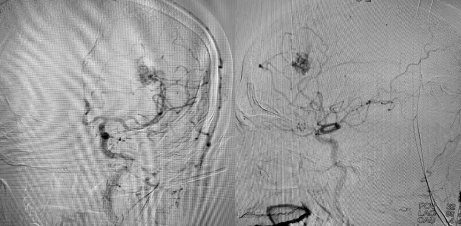

术前DSA

与患者家属详细沟通,征得家属同意后,即刻联系各相关部门开启卒中绿色通道。纪文军主任带领介入治疗团队立即对患者进行了全脑血管造影术,术中确诊为左额顶叶脑动静脉畸形。考虑到苏先生年轻,出血量大,供血动脉较为丰富,部位深,累及重要功能区,手术指征明确,纪文军主任团队为其量身制订了微创手术方案——经导管行脑动静脉畸形栓塞术。